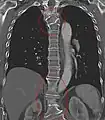

Butterfly vertebra (red). Normal vertebra for comparison (blue).

Volume rendering of a CT scan of the lumbar vertebral column, showing butterfly vertebrae at several levels, most typically in L1.